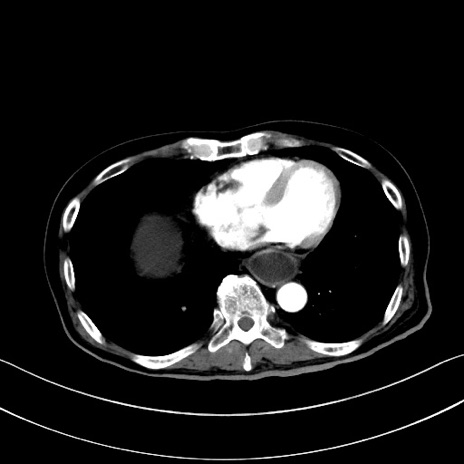

症例28(横断像)

【症例】60歳代男性

【主訴】嘔吐

【現病歴】胃癌にて胃全摘後。食思不振が悪化し、夜中に嘔吐することがある。

【既往歴】胃癌、胃全摘、脾摘、胆摘後

【データ】WBC 5900、CRP 10.56